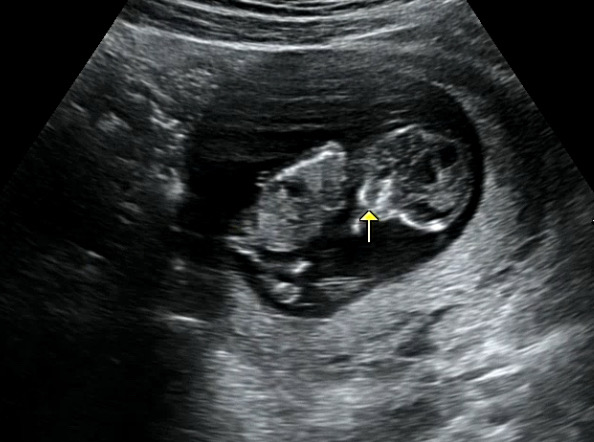

12주차입니다 아들일까요? 딸일까요? 고수님들 궁금합니다아아

아기가 다리로 생식기 돌기를 가리고 있어요.